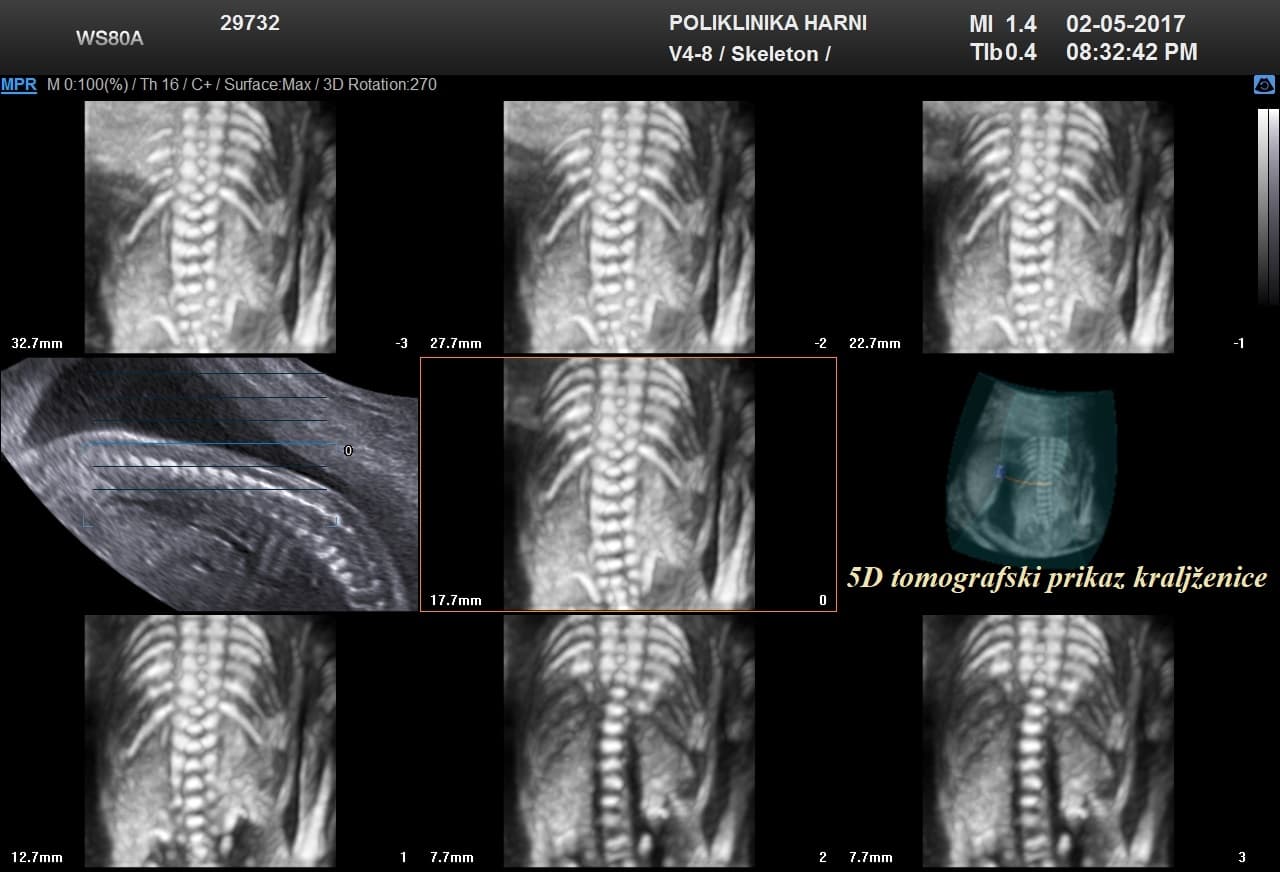

Oko 20. tjedna trudnoće obično se obavlja detaljan ultrazvučni pregled drugog tromjesečja, poznat kao morfološki ultrazvuk ili anomaly scan. Tijekom tog pregleda procjenjuju se razvoj i anatomija fetusa, razvoj mozga, srca i drugih organa, količina plodove vode te položaj i izgled posteljice.

Ovaj pregled omogućuje liječniku da procijeni razvija li se beba uredno te pruža važan uvid u tijek trudnoće, kao i da preporuči dodatne pretrage kao što su fetalna neurosonografija ili fetalna ehokardiografija.